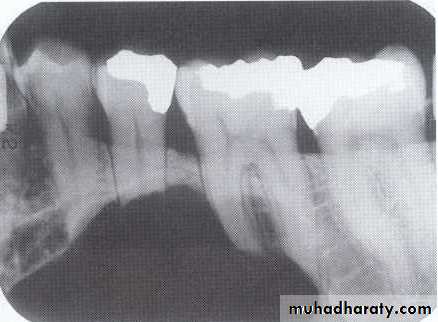

Radiolucency at apex of endodontically treated tooth

A: Radiolucent apical scar left after successful endodontic treatment..

B:New bone forming from the periphery of theLesion.

If the R.L.enlarged, pain,sinus,or no regression in the size of lesion after 6months (P. A. Cyst).

Apical scar